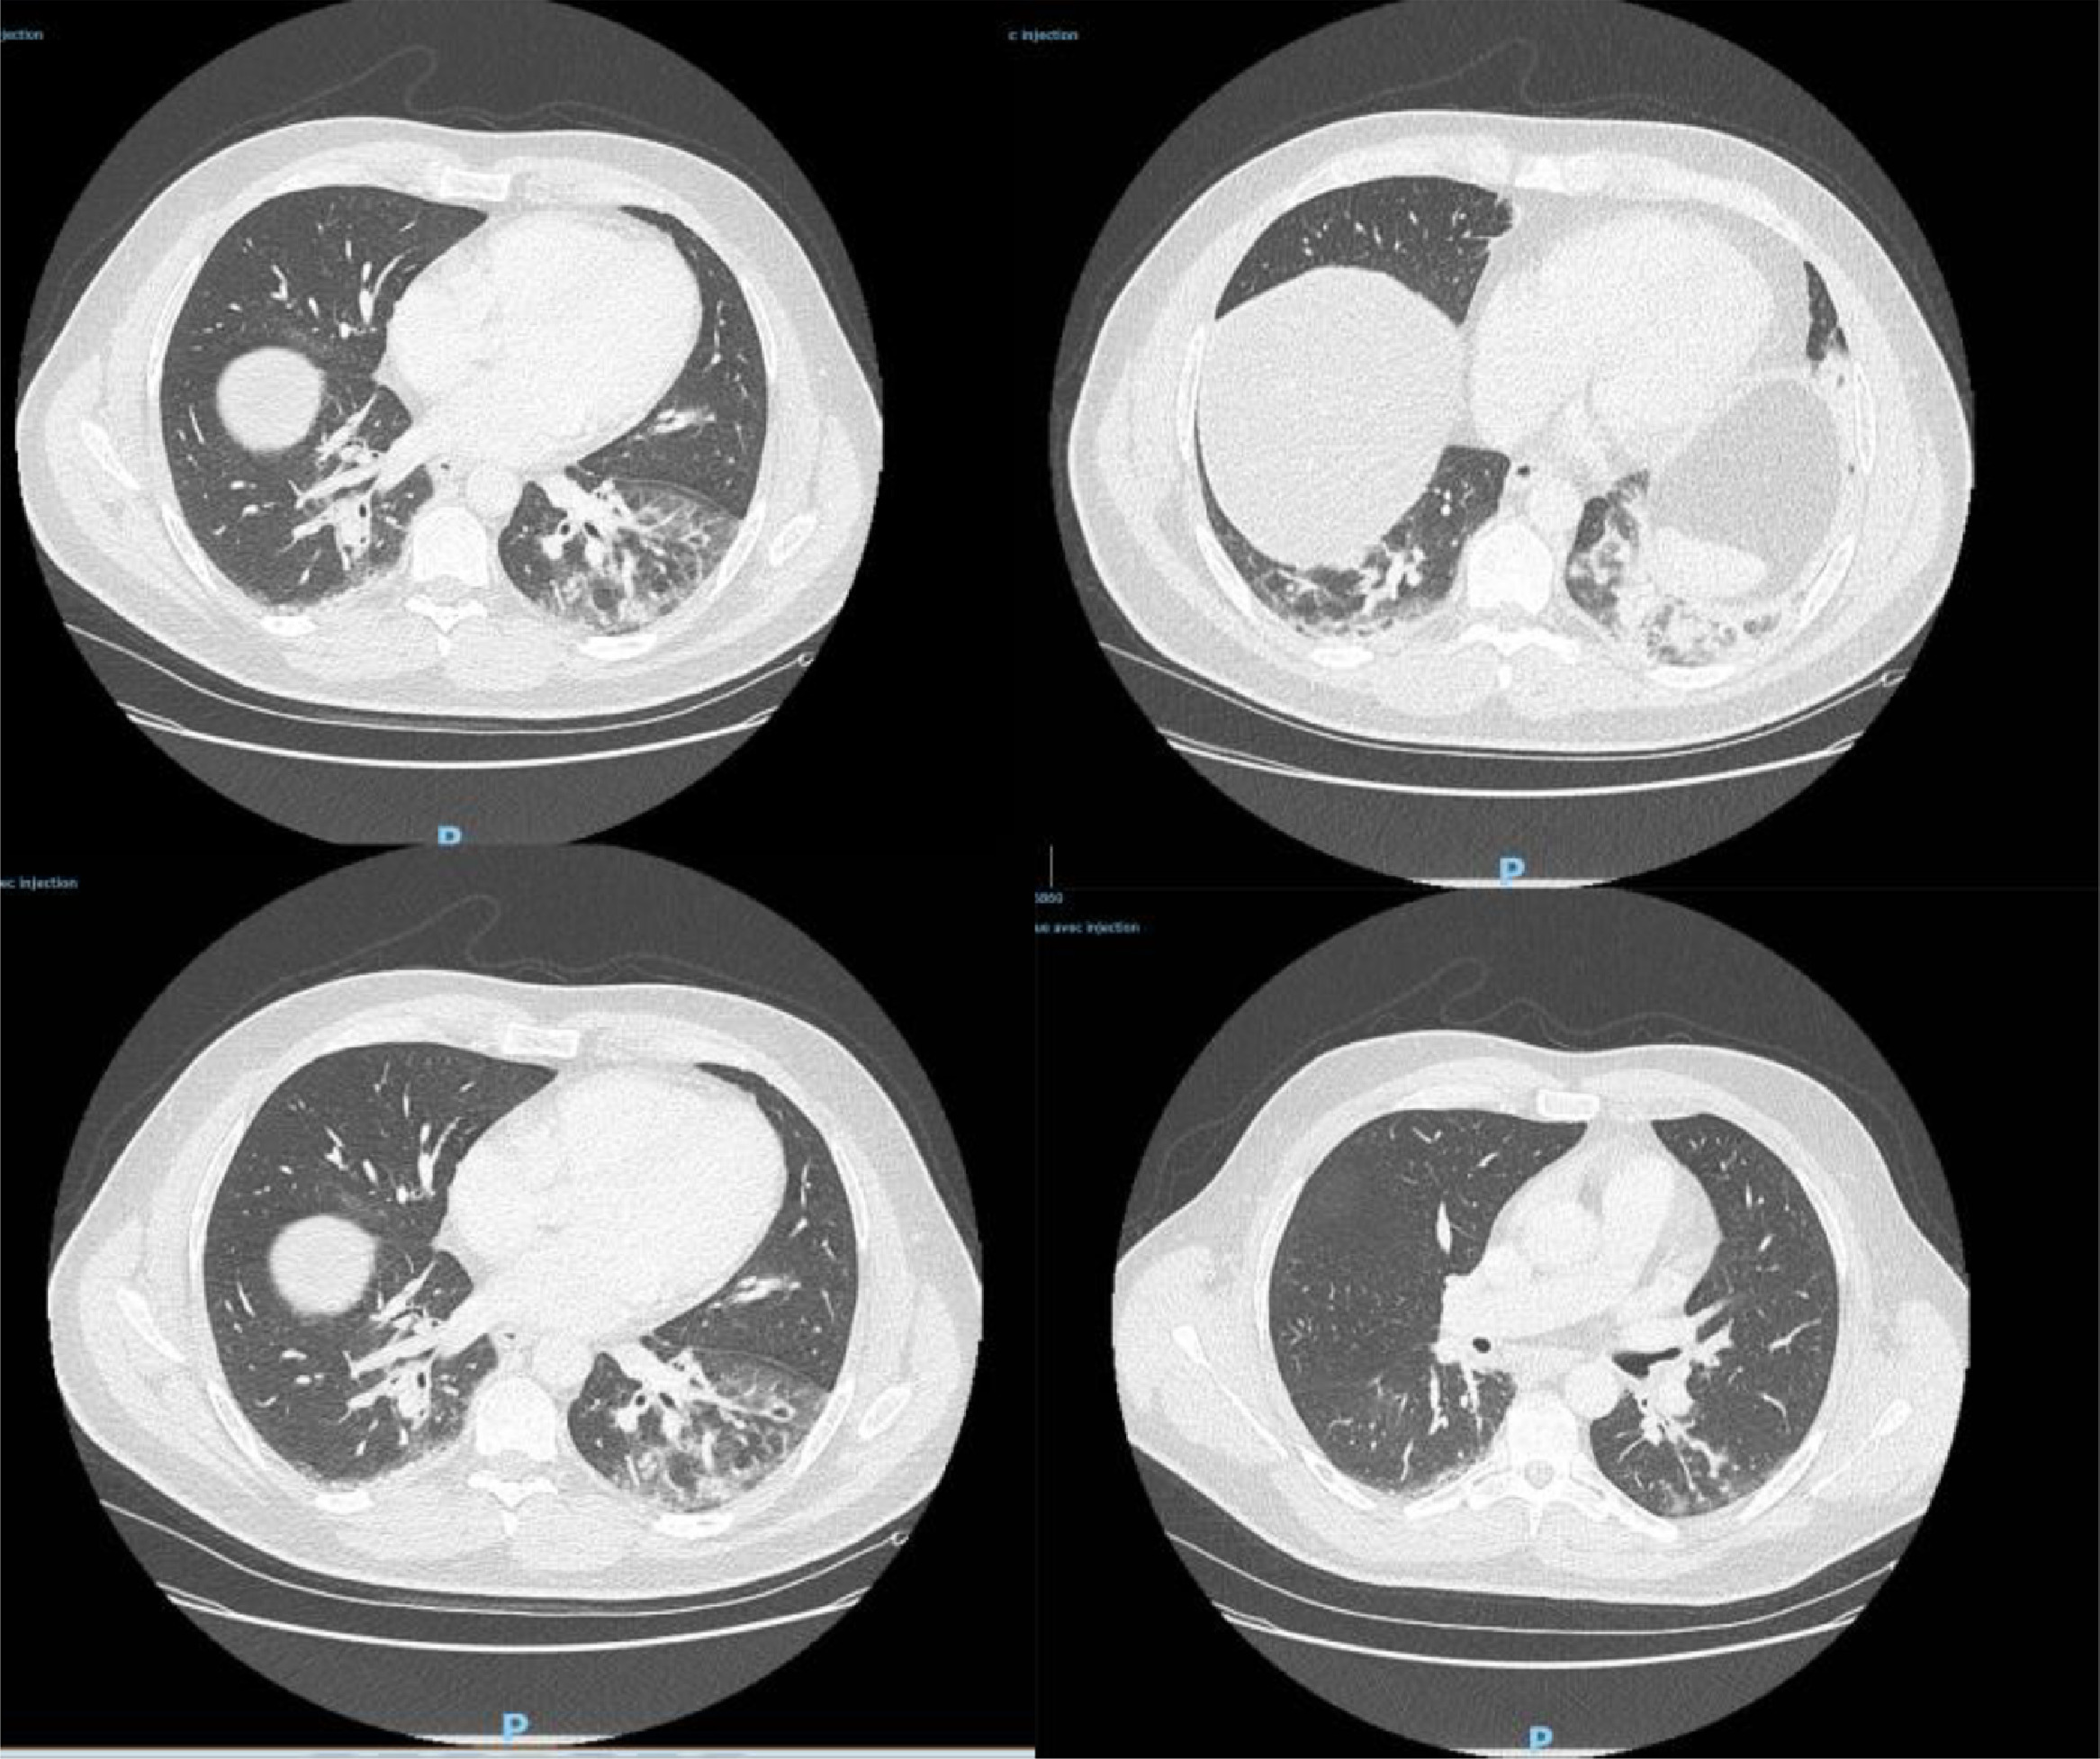

研究人员此番发现 , 一名42岁男子的样本新冠病毒检测呈阳性 。 该男子出生在阿尔及利亚 , 已长居法国多年 , 职业为鱼贩 , 最近一次旅行是在2019年8月前往阿尔及利亚 。 他于去年12月27日到急诊室就医 , CT检查显示双侧肺下叶呈现磨玻璃影 , 并伴有咯血、咳嗽、头痛及发热症状 , 且当时症状已持续4天 。 病患当天被收入重症监护室并进行抗生素治疗 , 后因病情好转于12月29日解除重症监护 。

△图为病患CT检测影像

论文指出 , 由于这一病例与中国缺乏关联 , 并且在发病前没有临近旅行史 , 这表明新冠病毒2019年12月底已在法国人当中传播 , 比2020年1月24日官方首次确诊病例早了近1个月 。 由此也可推测 , 在2020年1月期间法国或存在大量无症状感染者 , 他们造成了病毒的进一步扩散 。 论文还称 , 这一发现改变了对于法国新冠肺炎疫情发展的认知 , 此前相应的研究模型需要就此作出调整 。